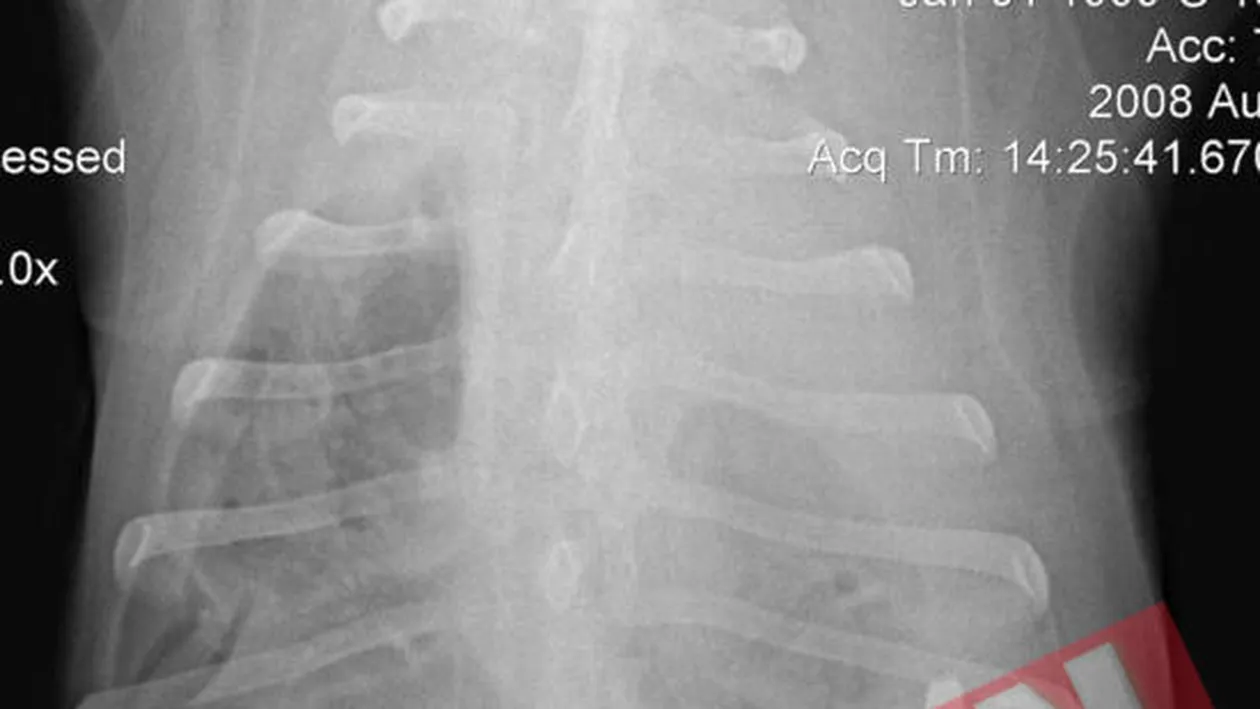

POFTICIOS. Apachee a infulecat cina oferita de stapani cu tot cu tacamuri Alina Creanga Pofticios din fire, Apachee, un husky in varsta de zece ani din Carolina de Nord, nu s-a putut abtine si a dat iama in cina stapanilor lui. Se pare ca patrupedul a fost atat de incantat de bucatele gasite pe masa, incat le-a inghitit dintr-o suflare, impreuna cu o furculita. Pentru ca timp de mai multe zile la rand catelul nu a dat semne ca ar fi ceva in neregula cu el, stapanii au ignorat incidentul si l-au dus la spital abia atunci cand Apachee s-a prabusit pe podeaua bucatariei, aparent fara nicio explicatie. In momentul in care veterinarii au hotarat sa ii faca o radiografie pentru a putea determina ce anume ii provocase animalului suferinta, acestia au avut o surpriza de proportii. „Nu ne-a venit sa credem cand am vazut furculita in stomacul lui Apachee. Starea lui proasta era determinata de faptul ca manerul ii perforase stomacul si ii traversase pieptul. Mai mult decat atat, furculita ii penetrase plamanul si ii sfasiase artera pulmonara”, a povestit chirurgul Gary Spodnick, care, impreuna cu echipa lui de sase medici, s-a luptat o noapte intreaga pentru a salva viata catelului. „Am fost la un pas sa il pierdem pentru ca a facut stop cardiac pe masa de operatie. Din fericire, am reusit sa il resuscitam, i-am facut transfuzii si am continuat operatia. Pot spune ca interventia chirurgicala a fost un succes”, a adaugat Spodnick, care a adaugat ca, in prezent, patrupedul se simte bine si a revenit la obiceiul de a infuleca tot ce ii iese in cale.